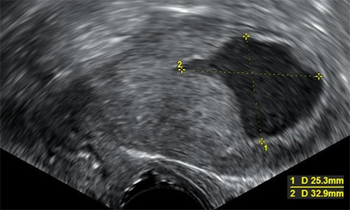

The combination of sentinel lymph node mapping and use of uterine intraoperative restrictive frozen section in patients with low-grade endometrial cancer can reduce the rate of complete lymphadenectomy without reducing the detection of lymphatic metastasis.